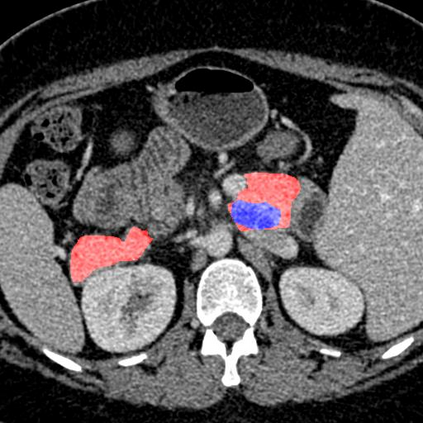

In this paper, we adopt 3D Convolutional Neural Networks to segment volumetric medical images. Although deep neural networks have been proven to be very effective on many 2D vision tasks, it is still challenging to apply them to 3D tasks due to the limited amount of annotated 3D data and limited computational resources. We propose a novel 3D-based coarse-to-fine framework to effectively and efficiently tackle these challenges. The proposed 3D-based framework outperforms the 2D counterpart to a large margin since it can leverage the rich spatial infor- mation along all three axes. We conduct experiments on two datasets which include healthy and pathological pancreases respectively, and achieve the current state-of-the-art in terms of Dice-S{\o}rensen Coefficient (DSC). On the NIH pancreas segmentation dataset, we outperform the previous best by an average of over 2%, and the worst case is improved by 7% to reach almost 70%, which indicates the reliability of our framework in clinical applications.